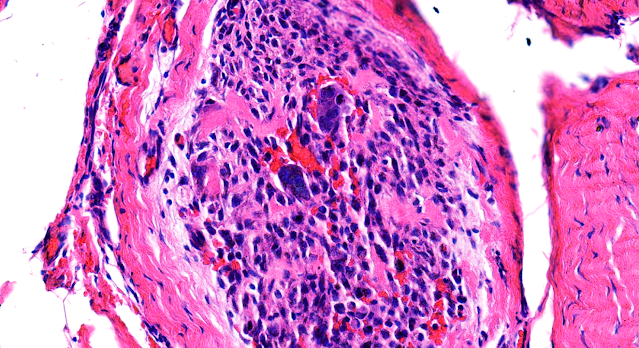

Dermatopathology Case 239 Get link Facebook X Pinterest Email Other Apps July 11, 2022 A 12 year old boy with a slow growing mass on the left upper limb. Answer Get link Facebook X Pinterest Email Other Apps Comments